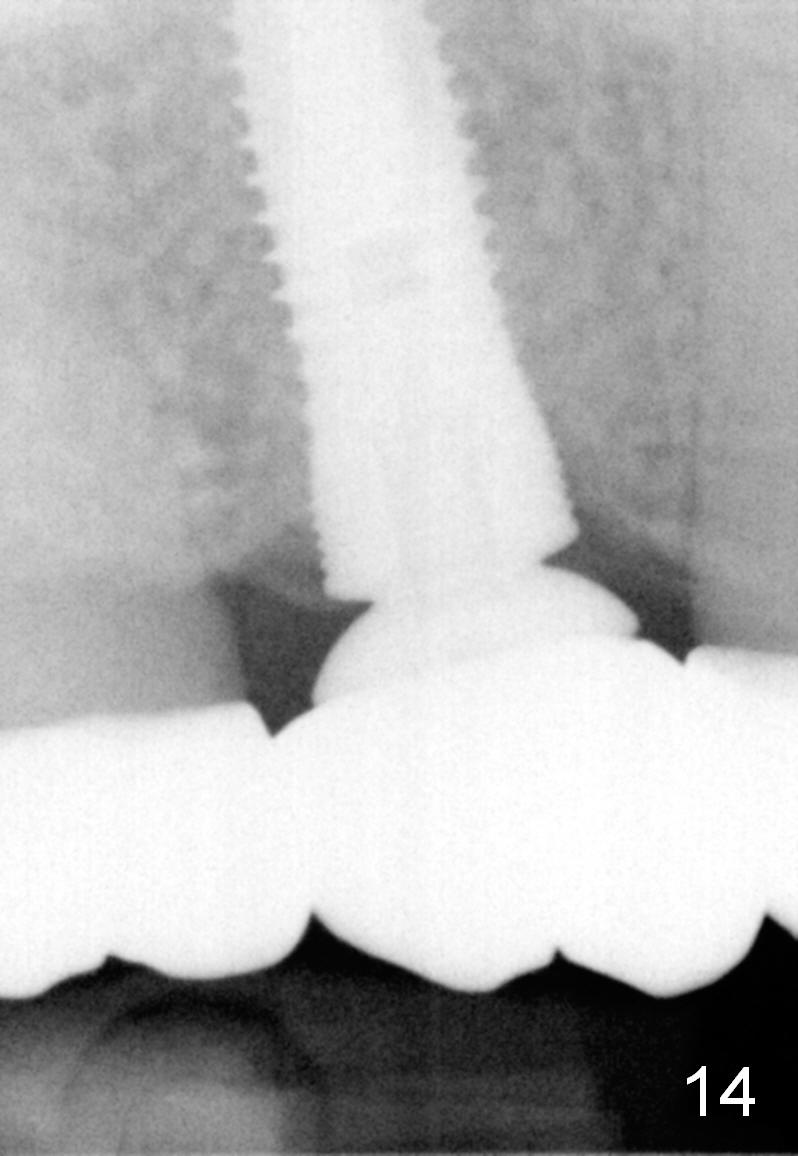

The bone density (Fig.1 white *) at the edentulous area (#3) is lower than that at the dentulous one (black *, 50 year-old man). The buccal plate is also atrophic and concave (Fig.2,3 arrowheads). A series of bone expanders are used to form osteotomy (following 1.6 mm pilot drill) at the depth of 14 mm (Fig.3 E 3.0 mm in diameter). When the last expander (4.3 mm) is removed from the osteotomy, the buccal plate appears to have been moved buccally (Fig.5 arrowheads). A 5.3x14 mm submerged implant (Fig.6 I) is placed with insertion torque >35 Ncm. The buccal plate seems to improve following placement of an 8.2 mm healing abutment and suturing (Fig.7). No bone graft is used. The buccal plate remains normal 12 days postop (Fig.8). It is slightly concave 3 months postop (Fig.9) with minimal bone resorption at the crest (Fig.10 (H: healing abutment),11 (A: cemented abutment). Nine months post cementation (12 months postop), bone resorption at the crest remains minimal (Fig.12) while the buccal plate (Fig.13 *) at #3 remains strong. Bone loss appears not to get worse 22 months post cementation (Fig.14). Soft and hard tissues remain healthy around the implant crown 3 years (Fig.15) and 3.5 years (Fig.16,17) post cementation.